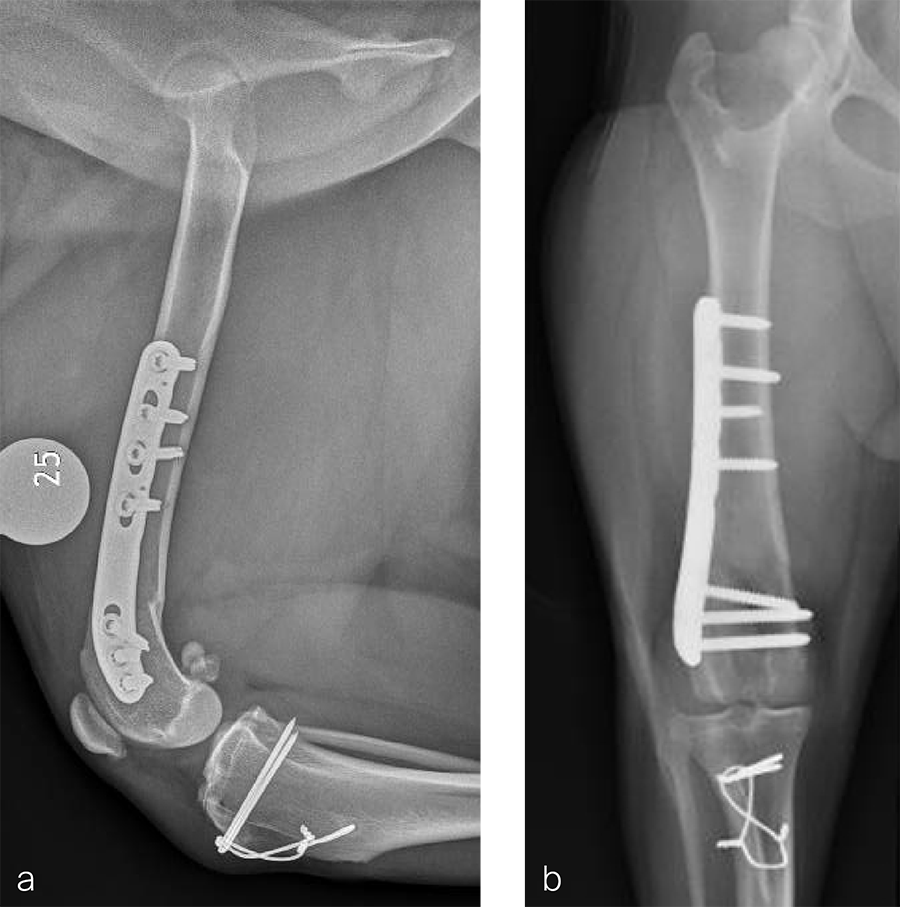

Fig 7a–b Initial surgery performed at 1 year and 6 months of age. The patellar luxation was treated with a lateral imbrication. No primary orthopedic procedures were performed. Radiographs were obtained six weeks postoperatively, and document persistence of the medial patellar luxation.

Fig 8a–b Revision surgery performed to address persistent patellar luxation. A tibial tuberosity transposition was performed to realign the insertion of the patellar tendon without addressing femoral deformity. Radiographs were obtained two months postoperatively. The patellar luxation persists despite transposition of the tibial tuberosity.